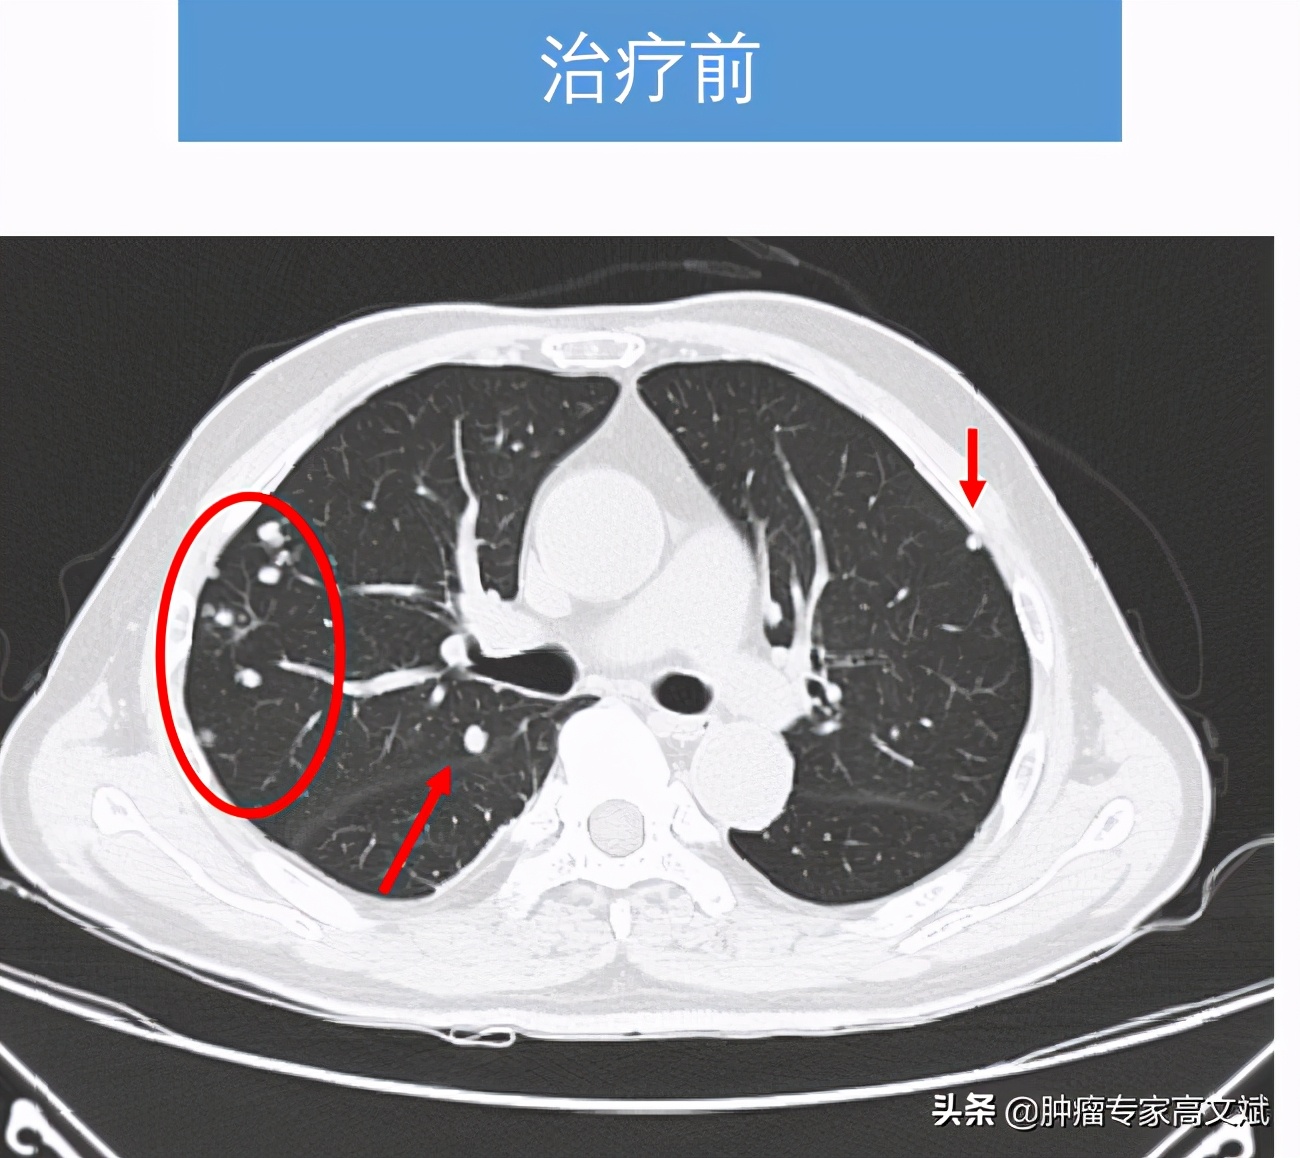

患者老陈今年58岁了,10个月以前在外院发现肝右叶占位,临床诊断为原发性肝癌,由于没有手术治疗的机会,患者在外院实施了一系列的非手术治疗,包括PVL、TACE治疗等,还口服了仑法替尼靶向治疗了2个多月。患者这边的治疗是一刻也没有停,肿瘤那边是生长也一直没有停,就这样患者来我们科的时候,肝右叶肿物较前已经是明显的增大、增多,肝右叶最大的肿瘤已经是16.2cm×10.7cm×9.5cm大小,静脉癌栓也增多,双肺出现了新发转移灶。由于持续性的治疗,患者对于治疗已经失去了信心,只是要求别让他太疼痛即可,茶不思饭不想的他已经不期待什么治疗的疗效了。

看着患者的一般情况还好,所谓的身体状况不佳主要还是前边治疗的不良反应所导致的。我们还是决定给患者实施一个单药的免疫治疗来控制肿瘤的生长,又不过分增加患者的不良反应。就这样患者也接受了我们的建议,我们为患者实施了国产的免疫制剂卡瑞利珠单抗(艾瑞卡)200mg,每2周一次使用。让我们没有想到的是,患者治疗2个周期以后,肿瘤标志物AFP出现了陡坡样的下降,肝脏疼痛也出现了缓解,每天躺在床上的老陈已经开始下床活动,饮食量等情况也明显的改善,对于治疗患者也有了明显的信心。就这样,治疗了8个周期以后,老陈的肝脏肿瘤明显缩小了,肺内转移灶也有消失,肿瘤标志物则是更早地恢复了正常,止痛药也完全的不再使用了。对于老陈来说,剩下的事情就是每月来罗湖医院肿瘤科输注两次卡瑞利珠单抗(艾瑞卡)就可以了。